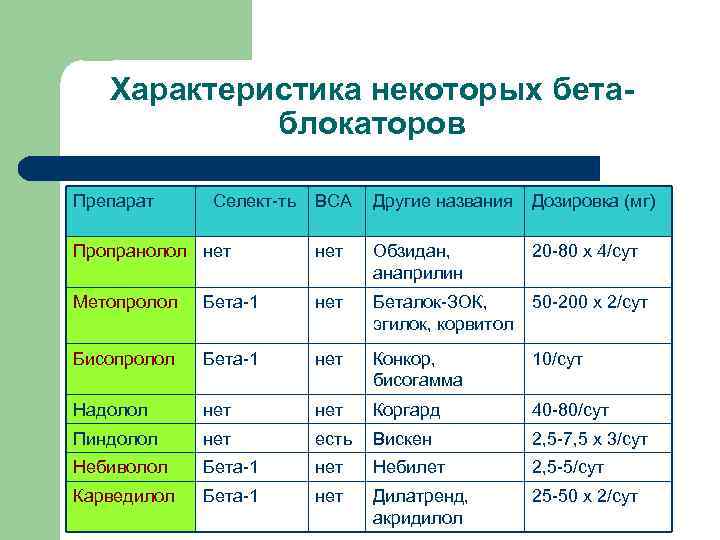

Кому – бета-блокаторы? Всем при отсутствии противопоказаний 2. Особенно перенесшим ИМ Какие? Селективные, без ВСА: l При сохр. ФВ – метопролол (сукцинат), бисопролол, пропранолол, небиволол l При сниж. ФВ – карведилол 1.

Свойства бета-блокаторов l l l Селективность (метопролол, бисопролол, небиволол) ВСА (отсутствует у всех рекомендованных) Сосудорасширяющий эффект (карведилол, небиволол) Липофильность (пропранолол, метопролол, бисопролол, карведилол) – не имеет клинического значения Период полувыведения: бисопролол – до 15 ч. , эсмолол – 9 мин.

Характеристика некоторых бетаблокаторов Препарат Селект-ть ВСА Другие названия Дозировка (мг) Пропранолол нет Обзидан, анаприлин 20 -80 х 4/сут Метопролол Бета-1 нет Беталок-ЗОК, эгилок, корвитол 50 -200 х 2/сут Бисопролол Бета-1 нет Конкор, бисогамма 10/сут Надолол нет Коргард 40 -80/сут Пиндолол нет есть Вискен 2, 5 -7, 5 х 3/сут Небиволол Бета-1 нет Небилет 2, 5 -5/сут Карведилол Бета-1 нет Дилатренд, акридилол 25 -50 х 2/сут